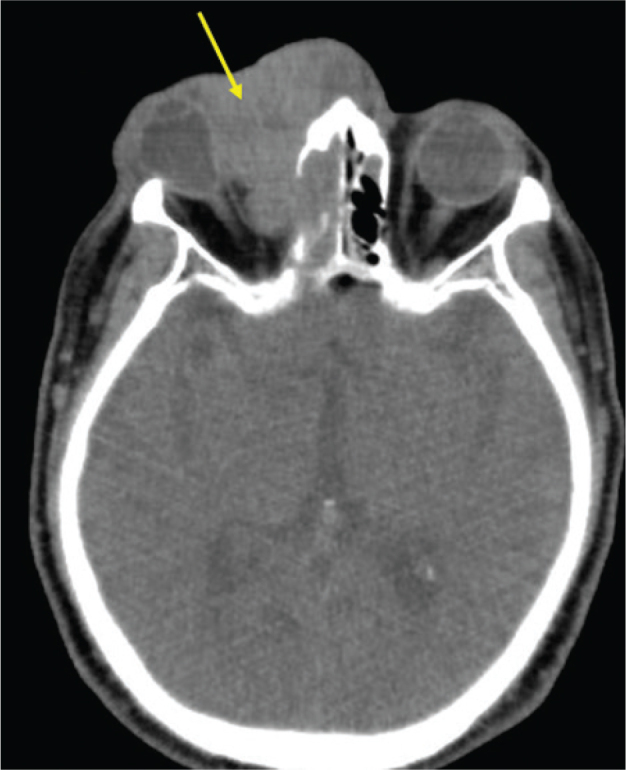

Skin Erosion on the Nasal Root with Marked Right Eyelid Swelling: A Quiz.